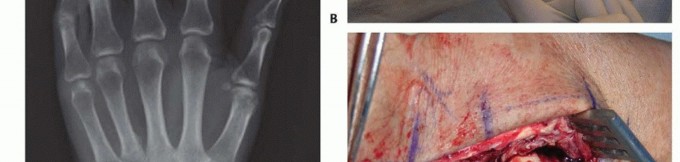

Volar Reconstruction for Mannerfelt Syndrome

On the volar aspect of the wrist, a distinct but equally devastating pattern occurs, known as Mannerfelt syndrome. Here, the flexor pollicis longus (FPL) and the adjacent flexor digitorum profundus (FDP) to the index finger are the most vulnerable. These ruptures are typically attritional, secondary to bony erosion from osteophytes at the scaphotrapezial articulation or the volar lip of the radius. The FPL tendon, tethered tightly against these bony prominences within the proximal carpal canal, undergoes ischemic and mechanical necrosis. Beyond mechanical attrition, the hypertrophic tenosynovium directly infiltrates the substance of the flexor tendons, causing an intratendinous rupture that leaves a frayed, disorganized collagen stump that is entirely unsuitable for primary end-to-end repair.